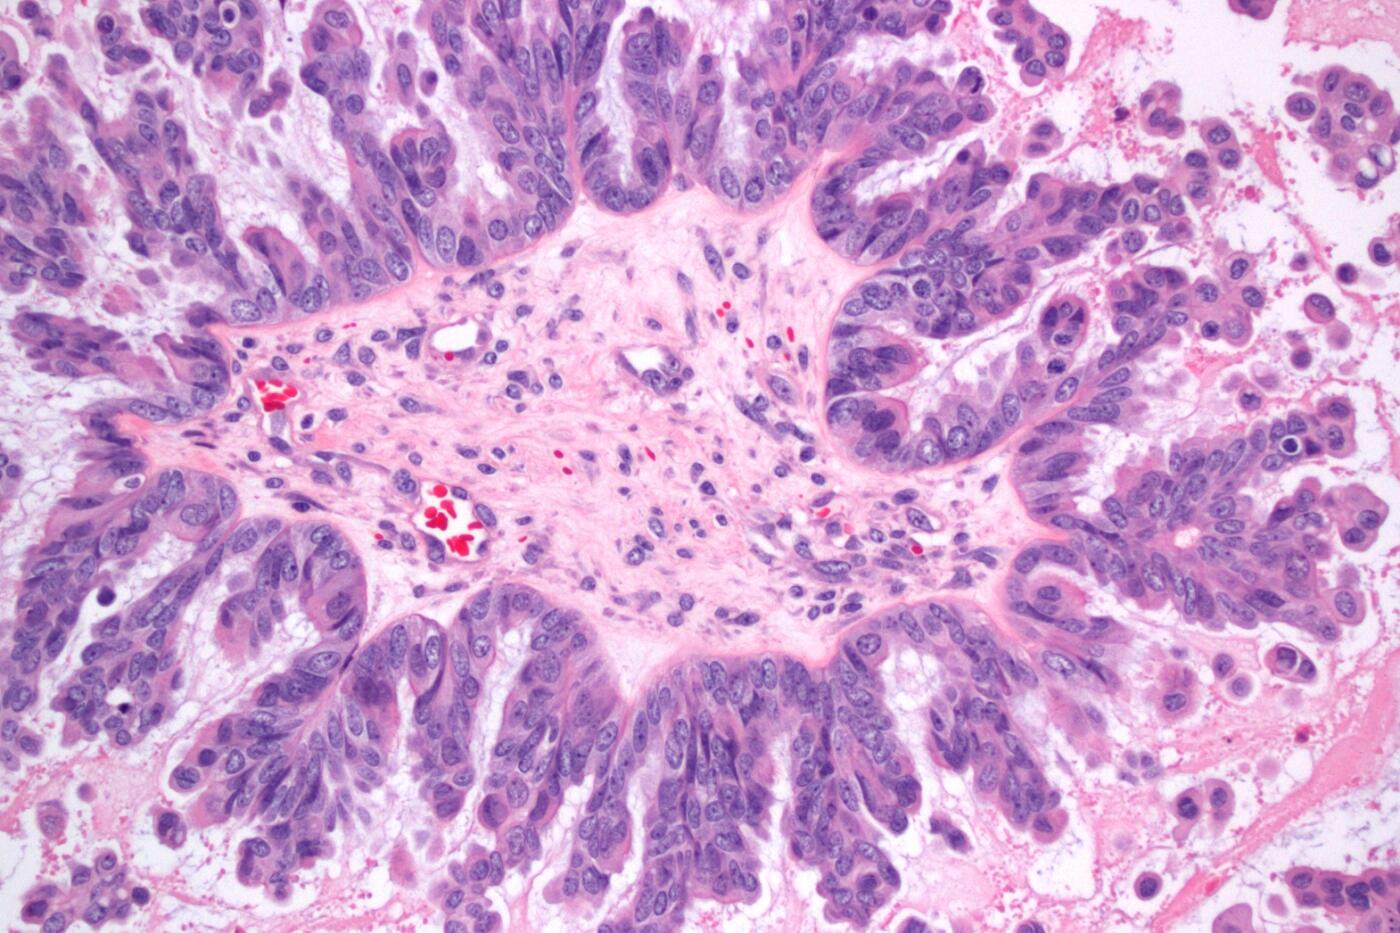

“A Serous Borderline Ovarian Tumor With Micropapillary Features”

Ema Dragoescu, M.D., assistant professor, Department of Pathology, School of Medicine

This image is of a hematoxylin eosin-stained section of an ovarian tumor at 200-times magnification. The cells surrounding the central core form thin, filiform micropapillae – an arrangement known as the “Medusa head” – that indicate aggressive behavior in the tumor.